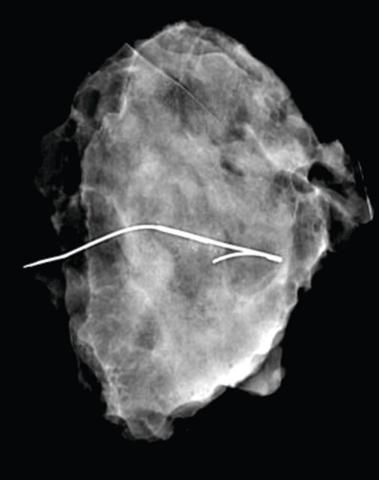

Røntgenbillede af lumpektomipræparat. Her ses nålemarkeringen midt i forandringen og med frie resektionsrande. Langs nålen ses et område med mikroforkalkninger.

Nålemarkering har over tid undergået flere modifikationer, mest nævneværdigt er modhagen, som blev tilføjet af Frank et al i 1976 [5]. Nålemarkering betragtes som guldstandard, da metoden er sikker, effektiv og associeret med lave omkostninger [2, 3, 6, 7]. Nålen skal placeres med spidsen midt i forandringen og kan anlægges vejledt af røntgen eller ultralyd. Når placeringen er bekræftet, trækker man kanylen ud, så nålen bliver tilbage (Figur 1). Kirurgen kan herefter peroperativt følge nålen frem til forandringens placering [7, 8]. Ved større nonpalpable forandringer såsom mikroforkalkninger over et større område placeres der ofte mere end én nål. Placering af nålemarkeringen sker på operationsdagen og varetages af radiologisk afdeling. Dette kræver en koordineret planlægning mellem radiologer og kirurger, og utilsigtede forsinkelser kan forstyrre operationsflowet [3, 6-10]. Fordi nålen forløber fra forandringen til hudoverfladen, kan placeringen være suboptimal i forhold til incisionsstedet. Derudover øges risikoen for forskydning i perioden mellem placering og kirurgi [3, 7, 9-11]. En præcis excision ved lumpektomi af en nålemarkeret forandring er ud over præcis placering af nålen også afhængig af kirurgens evne til at estimere nålespidsens placering [9, 11, 12]. Forskydning og suboptimal nåleplacering kan derfor føre til over- eller underexcision, som kan resultere i re-resektion og suboptimale kosmetiske resultater [2, 4, 10, 11]. En ekstra procedure på operationsdagen udsætter desuden patienterne for stress og angst ud over det, der naturligt er forbundet med en operation for brystkræft [2, 4, 6].